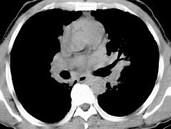

问题 男,38岁,咳嗽,咳痰,关节疼痛,外周淋巴结肿大,结合CT图像,最可能的诊断是 ( )

选项 A.肺泡蛋白沉积症 B.肺间质病 C.结节病 D.肺结核 E.霍奇金病

答案 C